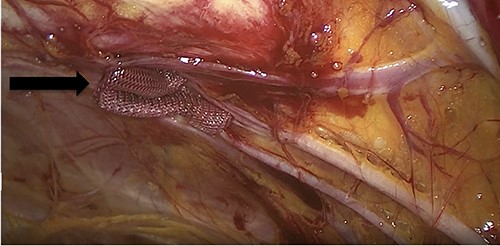

Due to the high-grade small bowel obstruction, the patient was pushed as an emergency case to the operating room. The surgery started and ended as a laparoscopic procedure with three small incisions; 12, 11 and 5 mm port sizes located supraumbilically, right and left midclavicular line relatively. Once the peritoneum was penetrated, and gas insufflated, diagnostic laparoscopy was done, and the obturator hernia with bowel content was visualized (Fig. 3), with a transitional zone at the hernia site showing a proximal dilatation and distal collapse of the small bowel. After that, reduction of the hernia content was subsequently made with no signs of gangrene or ischemia of the bowel. Then, the small bowel was run as a whole to eliminate any other transitional zones or pathology, which was unremarkable. Therefore, as there was no contamination, ischemia or perforation, a Vicryl mesh was elected and inserted as a plug into the obturator opening using a peritoneal flap and fixed (Fig. 4). Once the fixation was obtained, a ProGrip mesh was then applied to cover the whole right area (Fig. 5), which was covered by the peritoneum afterwards. The abdomen was inspected and the bowel looked healthy. Lastly, the ports were removed, the incisions were closed, the skin was clipped and then the dressing was applied.

An intraoperative figure of the right ProGrip mesh covering the whole right area.